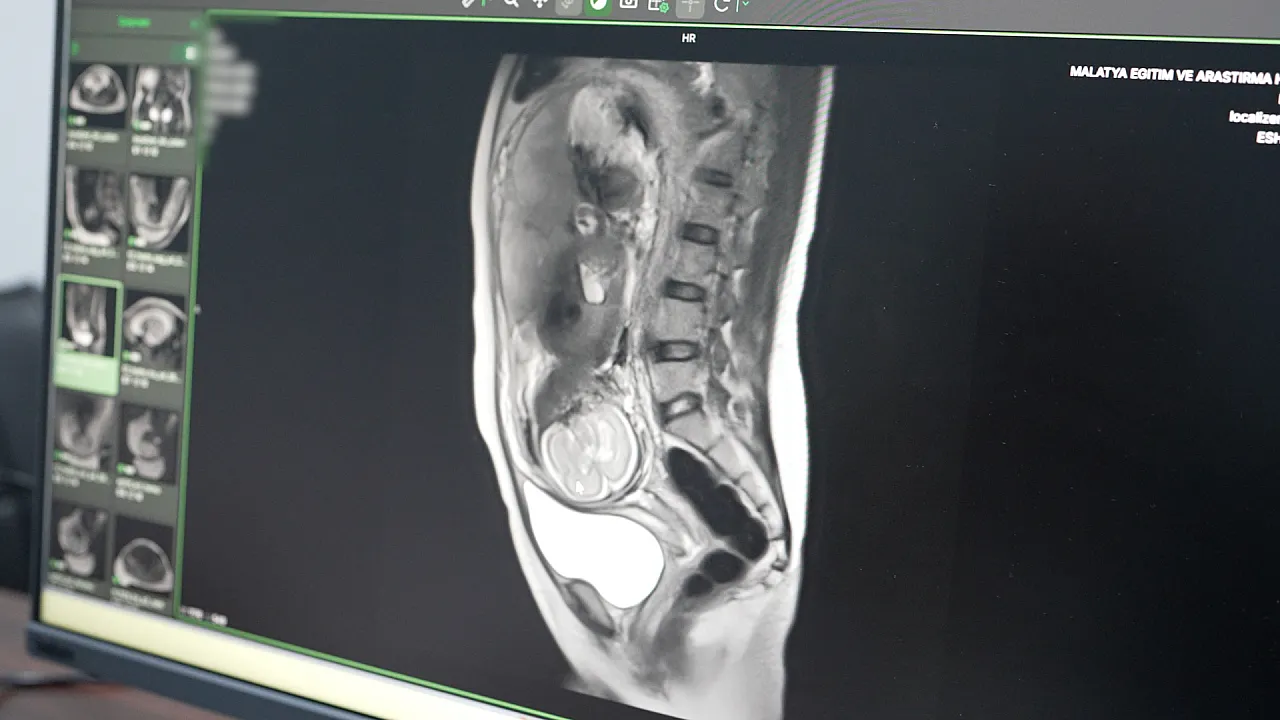

Hastanenin teknolojik atağı sadece kalp sağlığıyla sınırlı kalmadı. Daha önce yalnızca büyükşehirlerdeki tam teşekküllü merkezlerde yapılabilen "Multiparametrik Prostat MR" ve "Kardiyak MR" gibi özellikli işlemler artık Malatya’da rutin hale geldi. Özellikle anne adaylarını yakından ilgilendiren Fetal MR uygulamasıyla, anne karnındaki bebeklerin gelişimsel süreçleri ve olası anomalileri detaylıca incelenebiliyor. Bu yöntem, doğum öncesi planlamaların çok daha sağlıklı yapılmasına imkan tanıyor.